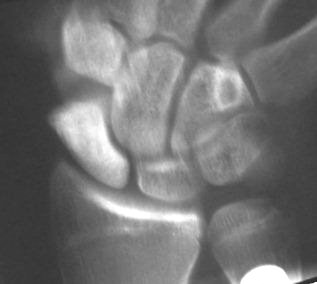

Clinical Example: Scaphoid fracture with total avascular necrosis similar to Preiser's disease

One of the problems with scaphoid fractures is ischemia of the proximal fracture fragment resulting in delayed union, nonunion or irretrievable avascular necrosis. In this case, ischemic changes involving the entire scaphoid are documented following a scaphoid fracture due to minimal trauma. This progressed with cystic changes and AVN on MRI. The patient had persistent pronounced wrist stiffness and pain. As pointed out to me by Dr. Lawrence Schneider (thanks!), this is technically not true Preiser's, for the fracture preceded the AVN.